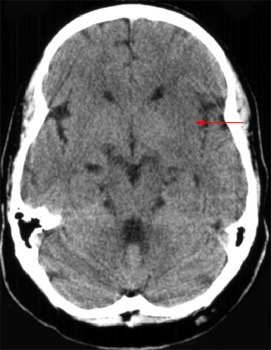

TC de crânio sem contraste, em corte axial, evidenciando obscurecimento do núcleo lentiforme (seta), com perda da diferenciação em relação ao hemisfério contralateral preservado, achado clássico de isquemia cerebral precoce em território da artéria cerebral média.

De 6 a 12 horas, a hipodensidade passa a se tornar mais evidente e a ocupar maior extensão do território. Surge o apagamento de sulcos, sinalizando edema em progressão, e o início de efeito de massa, ainda que discreto.

Entre 12 e 24 horas, a lesão já está estabelecida. A hipodensidade é clara, o edema é mais pronunciado, e podem aparecer sinais de compressão ventricular ou desvio da linha média nos casos volumosos.